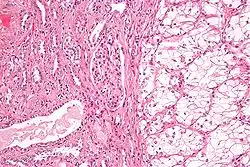

![]() | Bronchoalveolar carcinoma | Lepidic pattern of growth of tumor cells along the alveolar wall resembling butterfly sitting on fence. Normal alveoli is seen towards right side. | Category: Histopathology of bronchio-alveolar carcinoma | Bronchio-alveolar carcinoma |